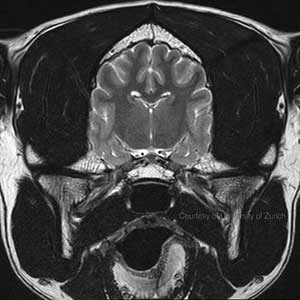

Wir sind zwei unabhängige Veterinärradiologinnen, die Ihnen gerne zur Seite stehen, wenn es um die Beurteilung und Durchführung von Bildgebenden Untersuchungen bei Hunden und Katzen, aber auch Heimtieren, Vögeln und Exoten geht. Wir beurteilen Röntgen-, CT- und MRT-Bilder und führen Ultraschalluntersuchungen durch.